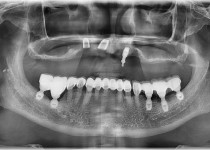

만 52세 전악 상악, 하악 전체 임플란트…